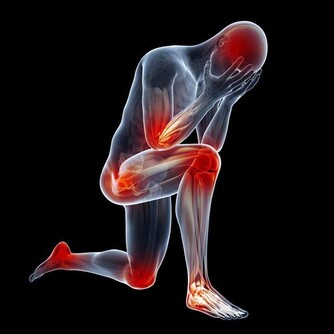

大多數肝癌患者都有肝區疼痛的症狀,具體疼痛的位置一般在右上腹,這是因為腫瘤迅速增大,使肝包膜受到了過度的牽拉之後引起牽拉痛,同時腫瘤的壞死物也會對肝包膜造成不同程度的刺激之後引起疼痛。也有一部分患者的腫瘤長在肝實質的深部,由於肝臟內部沒有痛覺神經,所以很少感覺到疼痛,但是在做了肝穿刺的檢查之後可能會導致癌結節破裂而引起劇烈的疼痛感。

肝癌晚期的患者會導致周圍組織受到破壞和浸潤,使附近的神經根被壓迫。比如癌細胞對橫隔造成影響之後就會使人的右肩或者右背部位出現疼痛感,有人的會以為這是肩關節炎,擅自使用消炎的藥物治療,但是服藥之後非但無法改善疼痛症狀,還會使肝病加重,疼痛感更強。